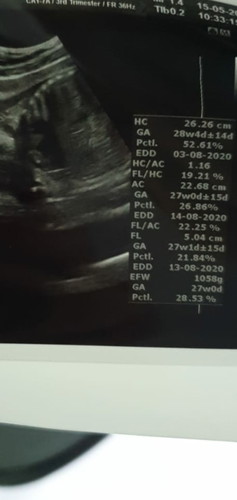

Im abit confuse with my latest scan. Im suppose to be 29 weeks that previous week when i went for scan... n edd from 1st aug to 3rd aug n now im seeing a 13 aug? .. now this is my latest results ... can someone advise for many weeks am i and whats my edd? Gynae didnt say anything. She just said everything is good and baby is not on the small side nor on the big side. Thank you.

It's normal to forget to ask or only noticing the details after the appointment! I would say just go with the original edd that was given. The biometric measurements are just estimations and it can give another edd based on that, it happened for my scans but I didn't read too much into it. If your gynae said everything is normal and on track, can just ignore whatever is on the ultrasound.

Read moreMine used to be the same cos i think the scan will adjust the dates according to the size of the baby.. nuthing to worry abt.. just follow the original edd ur gynae gave u. Baby will arrive when he/she’s ready